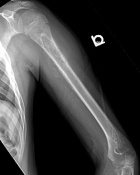

12 year old male c/o left arm progressive moderate pain x5 months, initially attributed pain to football injuries

Zoom image: Radiological image Radiological image.